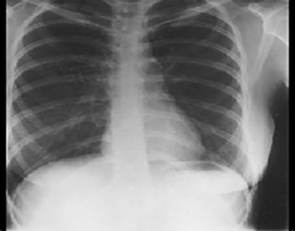

PA and Lateral

Click on the xrays to enlarge them.

Choose the best interpretation of the chest X rays:

Normal

Normal heart & lungs

with straightened spine

Normal heart & lungs with scoliosis

with pectus excavatum

Normal heart & lungs with kyphosis